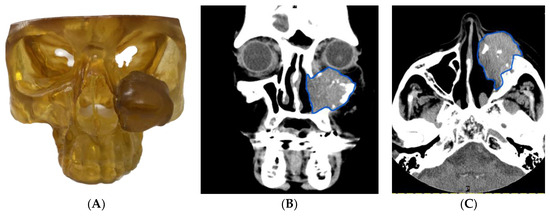

3.1.2. Case 2: Employing a 3D Model to Enhance Patient Communication